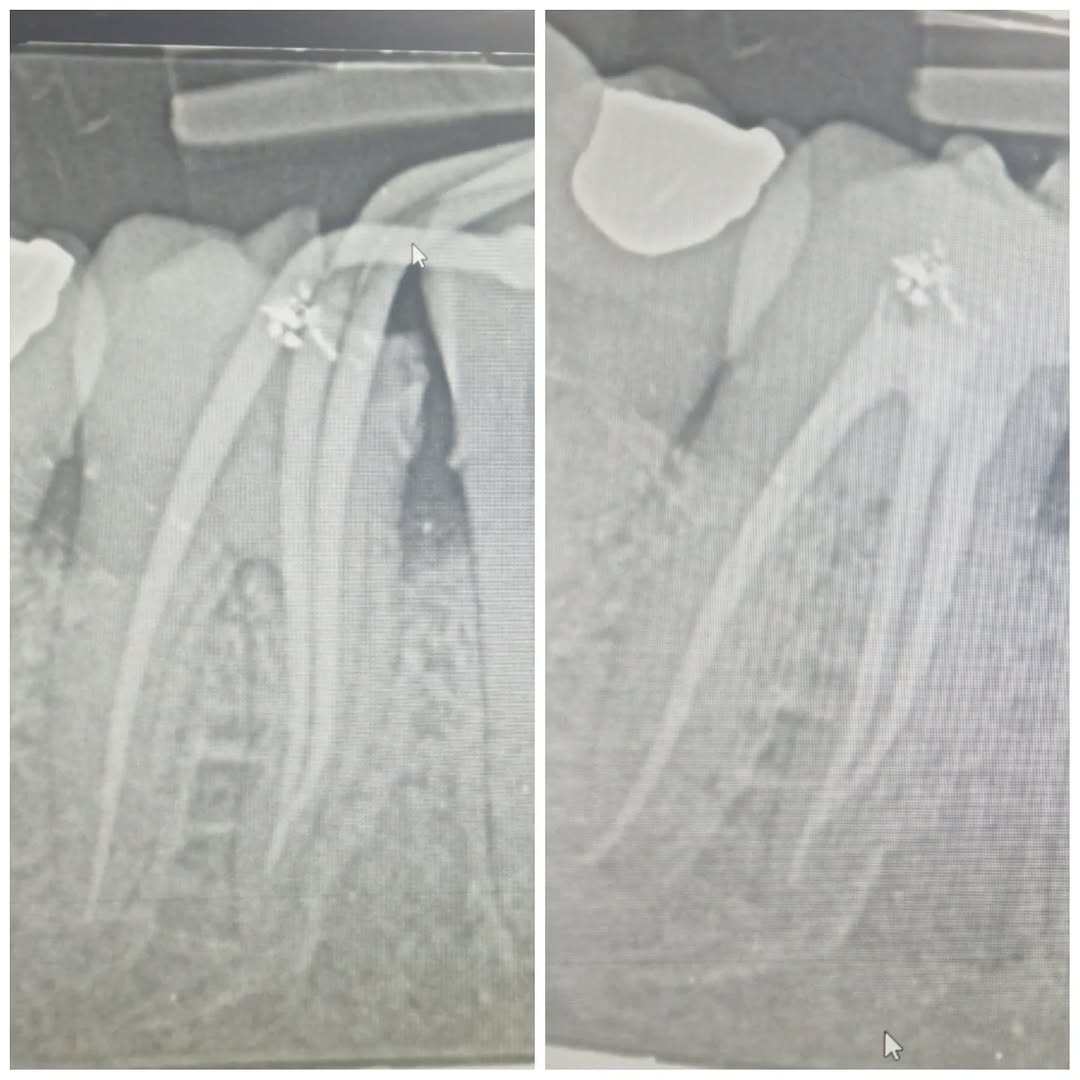

Male patient came in with severe pain on LR6 due to purulent pulpitis. Canals shaped with ProTaper Wave One Gold, GIC filling on top. P.S. : I've started enjoying this ???? #endodontist #protaper #waveon #molar #dentist

12